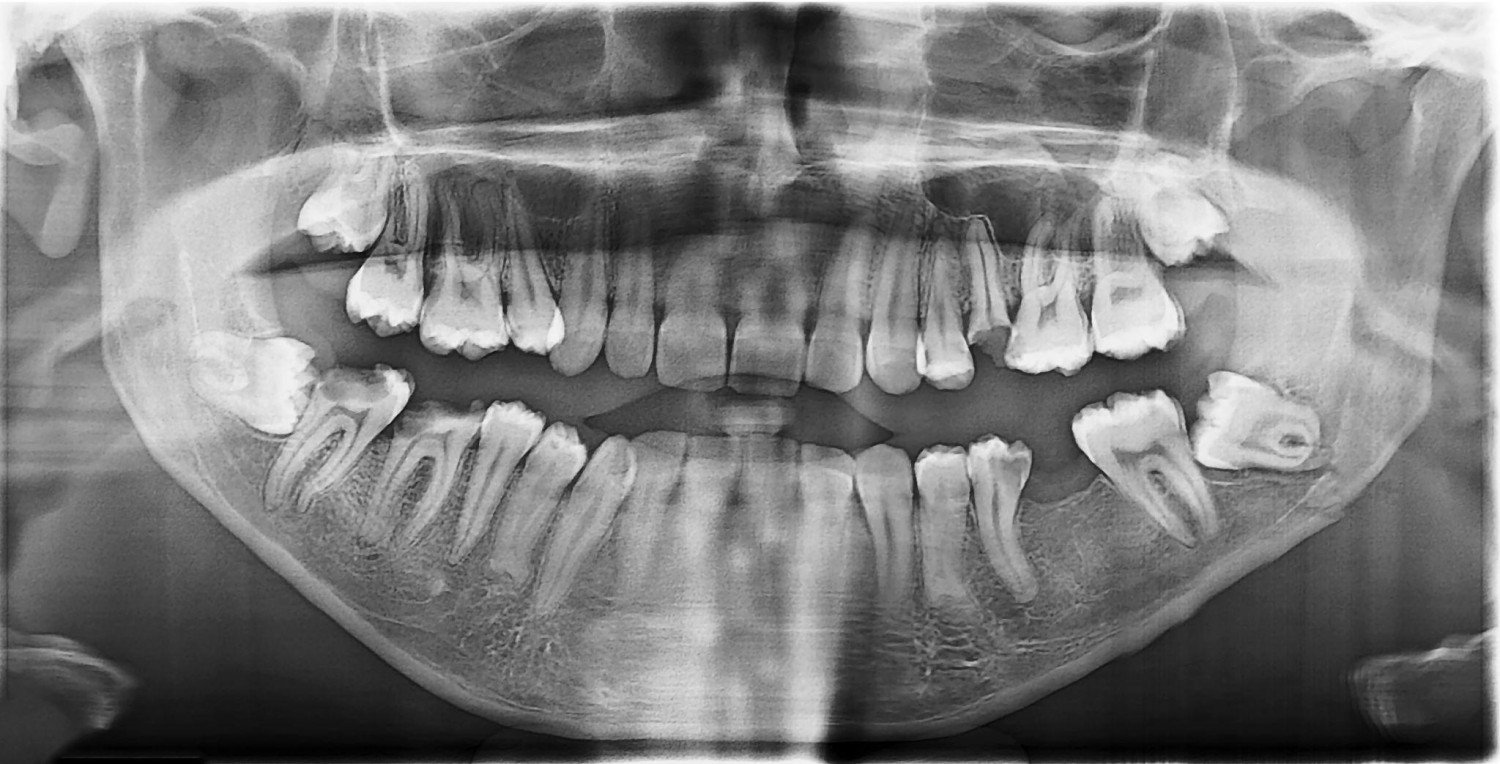

• Thăm khám và chụp phim trước khi nhổ

• Đánh giá vị trí răng khôn chính xác